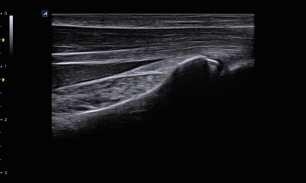

Hệ thống và đầu dò hiệu suất cao của E-CUBE 8 Series nhận ra hình ảnh độ phân giải cao. Hình ảnh rõ nét cao giúp bạn thực hiện khám nhanh hơn và chẩn đoán chính xác hơn.

Đầu dò độ phân giải cao

- Tuyến tính tần số cao: L8-17H / IO8-17

Các đầu dò tuyến tính tần số cao có thể được gắn vào E-CUBE 8 Series. Một số

Các tùy chọn chiều rộng dấu chân và chất lượng hình ảnh tuyến tính vượt trội giúp cho vú, tuyến giáp,

kiểm tra cơ xương và mạch máu.